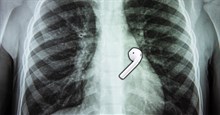

Người dùng @iamcarliiib đã đi tới bệnh viện để chụp X-quang và xác nhận rằng đúng là có một chiếc AirPod trong đường tiêu hóa của mình. Cuối cùng thì chiếc Airpods cũng rời khỏi cơ thể của cô nàng theo cách tự nhiên.